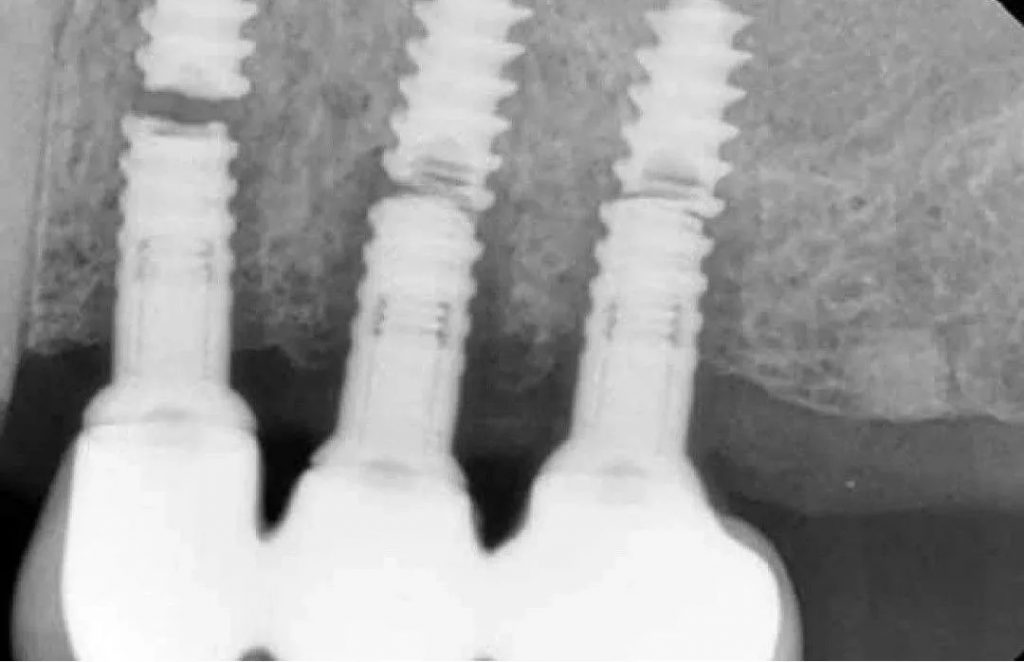

Bone Loss and Resorption

Bone loss can occur because of infection and inflammation, poor osseointegration (bone-implant fusion process), or excessive forces on the implant. Aging can also contribute to this problem. As a result of bone loss, the implant’s stability may be decreased and failure risk may be increased. To treat this issue, the dentist may perform bone grafting, which means transplanting bone tissue to the related area. You should avoid excessive force on the implants, maintain good oral hygiene and regularly visit a dentist to avoid bone loss.

Before taking a close look at dental implants’ suitability, let us briefly remind you how dental implants work. Dental implants consist of two components: the implant and the crown. The titanium implant integrates the jawbone through the osseointegration process and the crown serves as the visible part of the tooth. First, the implant is placed into the jawbone and the patient waits for 6 months for the implants to integrate into the jawbone. After the integration, the crown is placed on top of the implant.